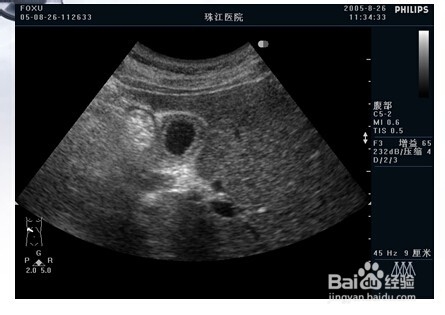

1、一:先天性胆总管囊肿。